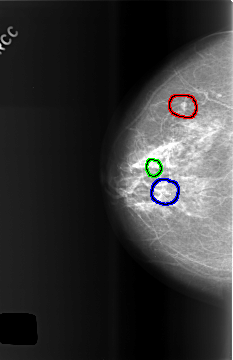

FILE: C_0508_1.RIGHT_CC.OVERLAY

TOTAL_ABNORMALITIES 3

ABNORMALITY 1

LESION_TYPE MASS SHAPE LOBULATED MARGINS CIRCUMSCRIBED

ASSESSMENT 2

SUBTLETY 5

PATHOLOGY BENIGN_WITHOUT_CALLBACK

TOTAL_OUTLINES 1

BOUNDARY

ABNORMALITY 2

LESION_TYPE CALCIFICATION TYPE PLEOMORPHIC DISTRIBUTION CLUSTERED

ASSESSMENT 3

PATHOLOGY BENIGN

ABNORMALITY 3

ASSESSMENT 4